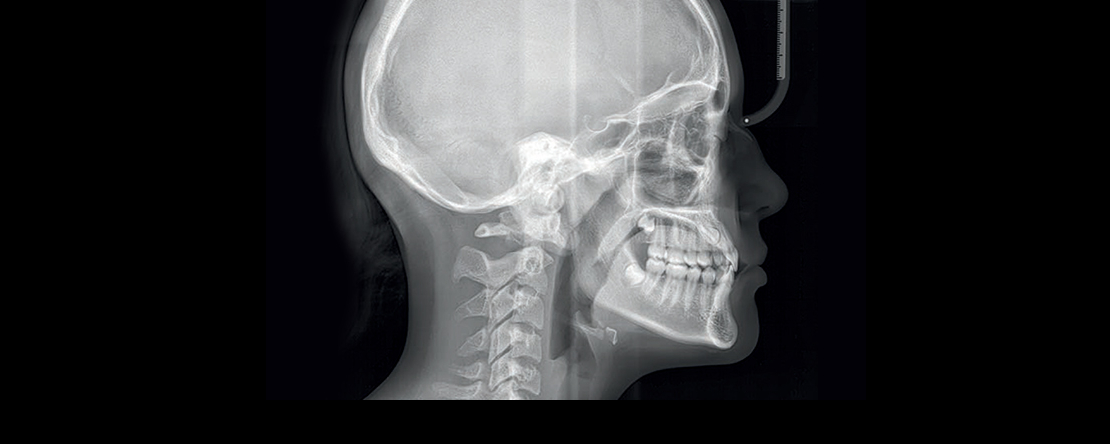

Os meios complementares de diagnóstico imagiológicos na esfera oro-maxilo-facial são sem dúvida uma ferramenta essencial para o diagnóstico e planeamento de cada caso clínico.

No entanto, muitos destes exames utilizam radiação ionizante pelo que não são inócuos para o paciente, devendo por isso ser selecionados e prescritos de forma criteriosa.

Outros existem, com e sem radiações ionizantes, específicos para determinadas patologias, ou inúteis para outras.

Como área em constante evolução torna-se indispensável conhecer as indicações e limitações de cada um destes exames, bem como a forma mais adequada de comunicar com o técnico de radiologia e o especialista que vai relatar o exame, de forma a garantir um exame com o máximo de valor de diagnóstico e o mínimo dano para o paciente.